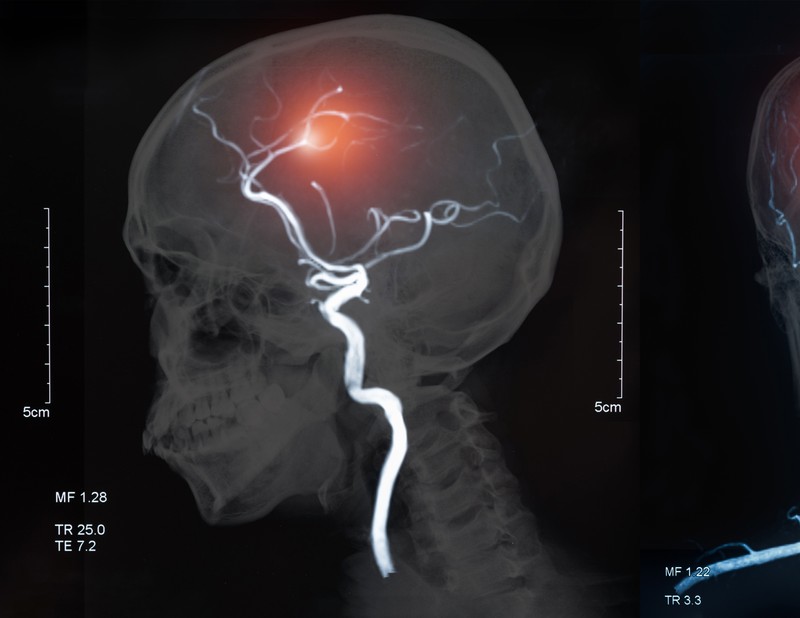

Agyvérzés